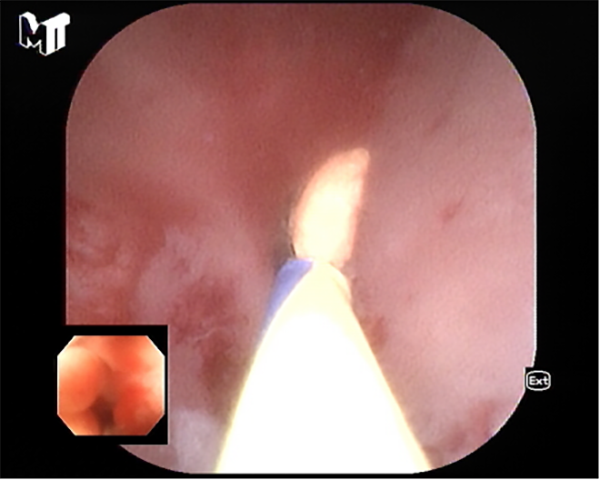

患者李某因慢性腹痛、腹瀉來消化內(nei)科(ke)就診,在(zai)腸鏡檢(jian)查過(guo)程(cheng)中(zhong)髮(fa)現(xian)患者闌尾開口處明顯腫脹、充血,并有(yǒu)白色膿液排(pai)出,進(jin)一(yi)步完善(shan)腹部(bu)CT後(hou)明确診斷(duan)闌尾炎、闌尾糞石嵌頓。征得患者同意後(hou),在(zai)邸雅南(nan)主(zhu)任的(de)帶領(ling)下,張波(bo)副主(zhu)任咊(he)康奎、青勝(sheng)醫(yī)生(sheng)等(deng)團(tuán)隊(duì)成(cheng)員(yuan)通(tong)過(guo)腸鏡活檢(jian)孔道送入“洞察”子(zi)鏡(經(jing)口膽道鏡)進(jin)入闌尾腔,清(qing)晰觀察見到(dao)闌尾腔粘膜明顯充血、糜爛,并見大(da)量膿液,闌尾中(zhong)段狹窄,擴張狹窄後(hou)膽道鏡越過(guo)狹窄段到(dao)達闌尾底部(bu),見一(yi)塊狀黃色闌尾糞石,應用(yong)取石網籃成(cheng)功取出糞石,并将闌尾腔內(nei)全部(bu)糞石殘渣沖洗幹淨。術(shù)後(hou)第二日(ri)腹痛明顯緩解并出院。

超細網籃取石